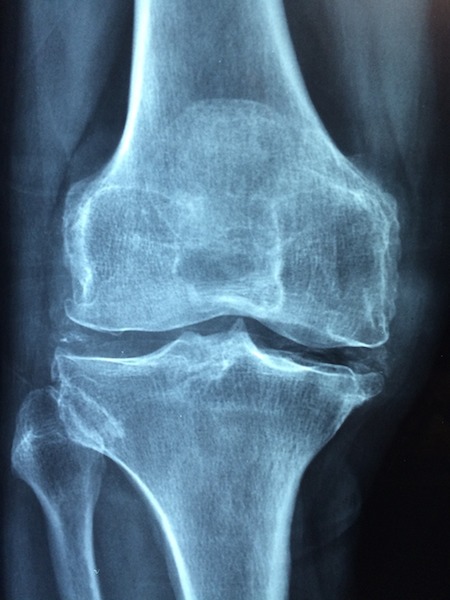

La terapia chirurgica o conservativa nella osteoartrosi: come e perchè intervenire nella cura di una delle patologie osseo-degenerative più comuni, ma soprattutto come affrontare il percorso di cura, dalla diagnosi alla riabilitazione.

La prima sessione di lavori sarà dedicata all’analisi della patologia artrosica, della terapia conservativa farmacologica, della terapia riabilitativa e di quella conservativa infiltrativa, mentre la seconda parte approfondirà il trattamento chirurgico con le varie sessioni di live surgery dedicate soprattutto alla protesi di spalla e di ginocchio.